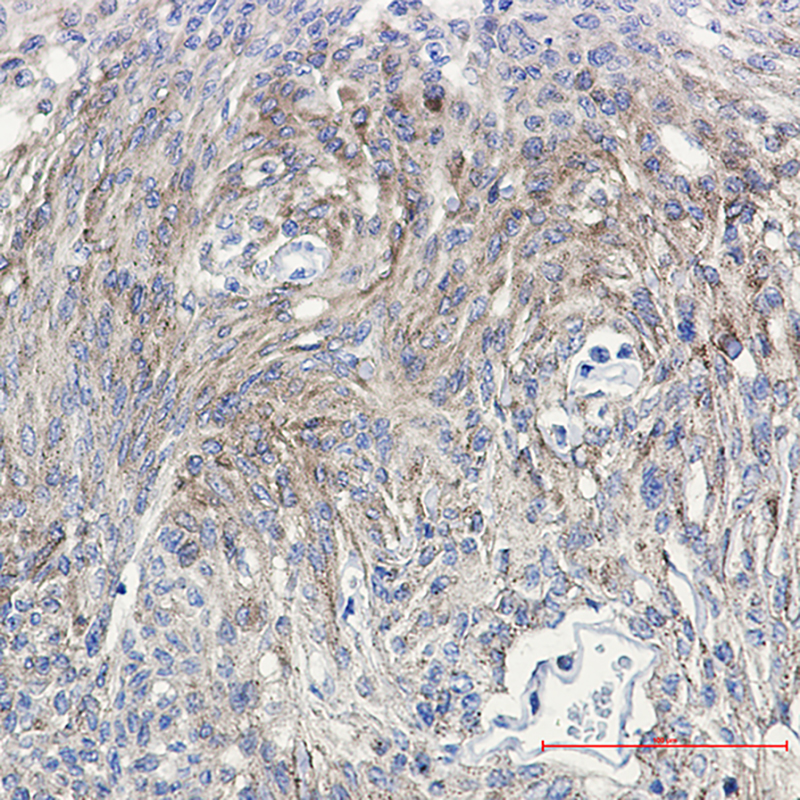

- Immunohistochemistry analysis of paraffin-embedded Human Brain using PKC (Phospho-Thr514) antibody. High-pressure and temperature Sodium Citrate pH 6.0 was used for antigen retrieval.